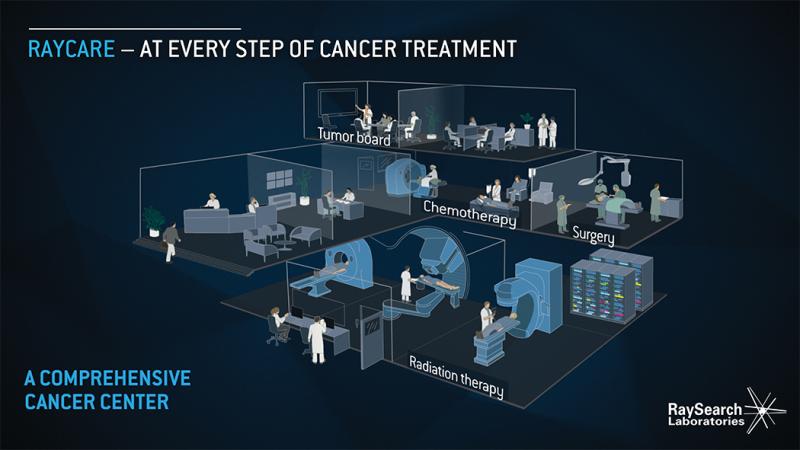

Provision, located in Knoxville, Tenn., is the latest to partner with RaySearch Laboratories on the development of its next-generation oncology information system (OIS), RayCare.

As one of the more precise methods of delivering radiation therapy for cancer treatment, proton therapy has grown at a rapid pace the last several years. Considered experimental not too long ago and used primarily in research settings, clinicians across the globe are rapidly coming to accept the utility of proton therapy for numerous indications — a list that many expect to continue to grow rapidly.

Cancer is perhaps the most highly personal, complex disease in our world today. While the various types of cancer are ...

University Medical Center Groningen (UMCG) is one of the largest hospitals in the Netherlands. The hospital provides world-class patient care and is engaged in cutting-edge scientific research and medical education. UMCG is a leading cancer center and will soon open a new state-of-the-art proton therapy center.